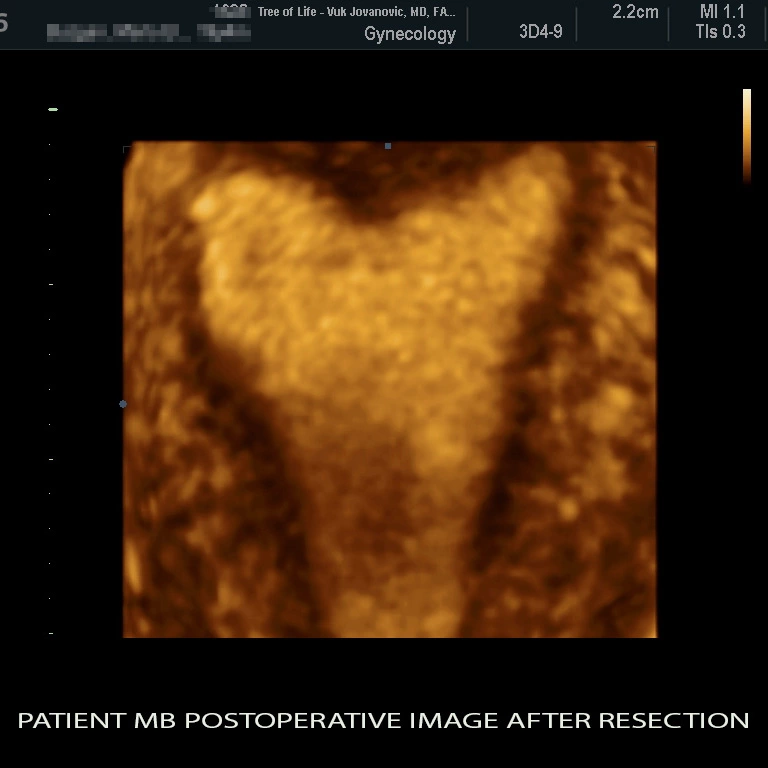

At the Tree of Life Center, we use a 3D vaginal ultrasound to determine the extent of the uterine anomaly and create a 3D picture of the uterine cavity. Our software allows us to rotate the virtual image of the uterus in any dimension so that all issues are clarified. The 3D ultrasound allows for three dimensional reconstruction of the uterine cavity with visualization that is superior to an HSG and can clearly identify the uterine septum. While a good sonographer might recognize a septum on 2D ultrasound, a detailed visualization and image post-processing can only work with a 3D ultrasound device. In comparison, the HSG fills out the cavity with contrast and utilizes low dose radiation. We see a lot of images taken in the wrong plane and the uterine shape can not be clearly seen on some studies. The HSG can not really adjust the plane and it mainly depends how your uterus lies in the abdomen. The 3D sonography can rotate the image using computer post-processing of the ultrasound data into the desired plane. Therefore, regardless how your uterus is positioned during the ultrasound acquisition, the correct plane can be adjusted. In addition to finding the right plane, the ultrasound will visualize the myometrium (the muscular layer that surrounds the cavity). This again allows us to see the uterine cavity and the entire uterus around it! The 3D sonography is therefore only comparable to a uterine MRI. However the MRI is very expensive and patients need to inject Gadolinium as a contrast medium and stay in the tube for a prolonged period of time. Some patients need to abort the MRI due to not tolerating the confined space or the IV contrast medium.We have included an image No.1 of a patient who was diagnosed with a uterine septum at our Tree of Life Center Los Angeles fertility clinic. We went ahead and did a surgical resection of the uterine septum and the image No.2 after surgery is included. A tiny residual where the septum was can still be seen, but the large indentation and Y-form cavity has been surgically corrected.